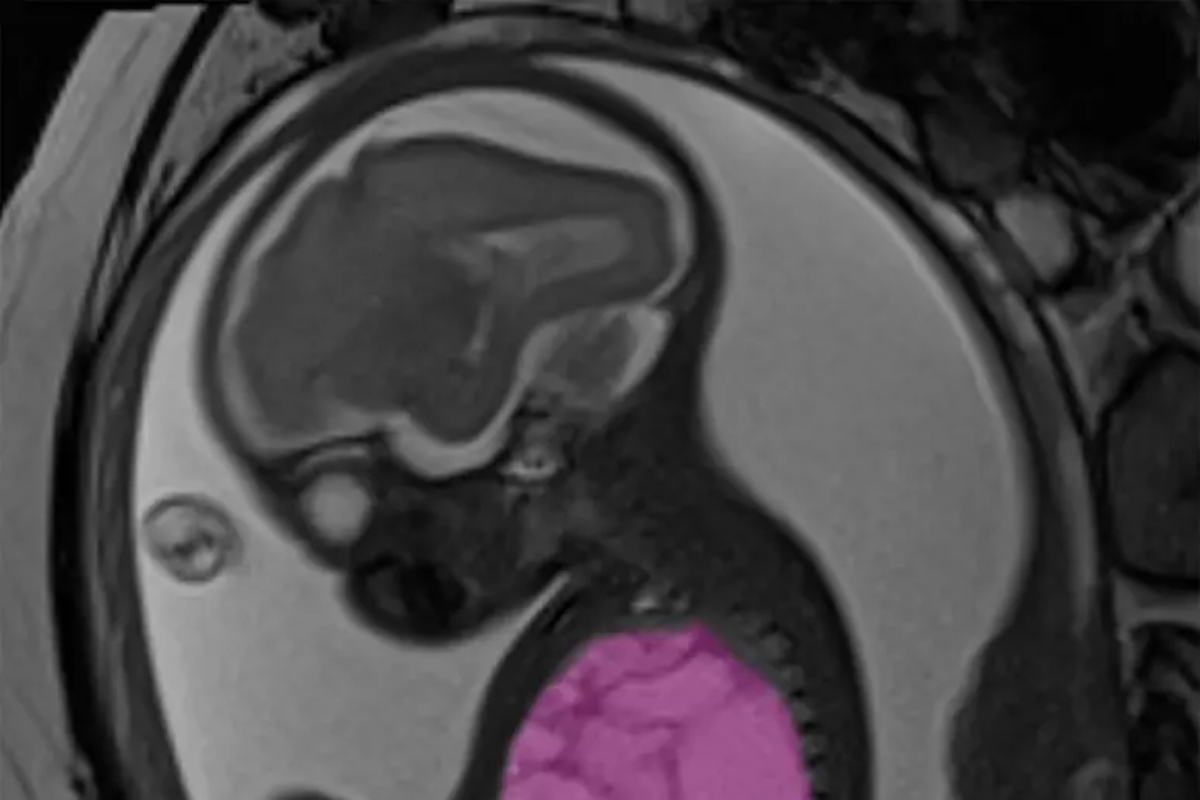

Operato ancora nel grembo della madre, lo salvano togliendogli una cisti polmonare grande come un'arancia (foto Ansa-Blitzquotidiano)

È una storia a lieto fine quella del piccolo Alessandro (nome di fantasia), operato quando era ancora nel grembo della mamma, una 35enne di Roma, per la presenza di una cisti polmonare grande come un’arancia che comprimeva cuore e polmoni, causando un grave scompenso cardiaco fetale che ne metteva a rischio la sopravvivenza.

Il delicato intervento è stato realizzato dall’équipe di chirurgia fetale dell’ospedale pediatrico Bambino Gesù di Roma durante la 24esima settimana di gestazione, dopo che la diagnosi prenatale aveva rivelato la presenza una voluminosa cisti polmonare congenita di circa 9x6x5 centimetri.